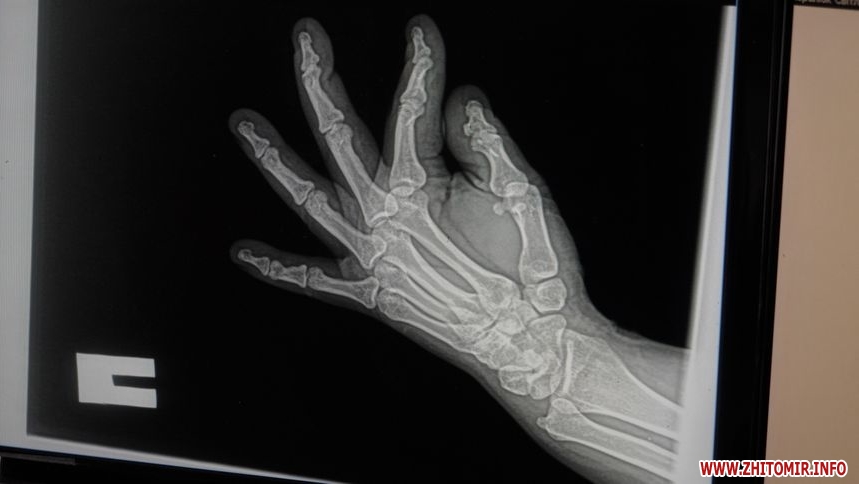

«Зараз розпочинається сезон, люди частіше використовують цю техніку і, відповідно, отримують травми. Цього року звернень ще не було, у минулому році зафіксували близько 30 звернень. Найпоширеніші – переломи верхніх кінцівок, переломи променевої кістки у типовому місці та кісточок гомілки. Було кілька випадків, коли травми потребували оперативного втручання та металоостеосинтезу», – розповідає в.о. завідувача ортопедо-травматологічного відділення КП «Лікарня №1» Житомирської міської ради Олександр Зубенко.